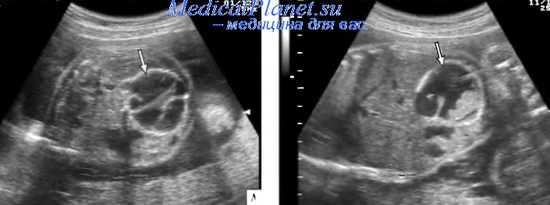

Наиболее характерными эхографическими признаками мекониевого перитонита являются кальцинаты брюшной полости, изолированный асцит, расширение петель кишечника, многоводие и псевдокисты. Обычно диагностика кистозного типа МП не вызывает затруднений. Эта форма характеризуется наличием псевдокисты в виде образования повышенной эхогенности схорошо очерченным гиперэхогенным контуром. Частота обнаружения псевдокисты составляет от 15,8 до 64,5%. Для этого типа МП характерен также асцит.

При генерализованном типе обычно обнаруживается многоводие, асцит, множество кальцинатов в брюшной полости. Передняя брюшная стенка может быть утолщена за счет отека. Фиброадгезивный тип характеризуется расширением петель кишечника. Кальцинаты брюшной полости - наиболее характерный признак, так как обнаруживаются с частотой 25-94,1% (в среднем 56%). Расширенные петли кишечника визуализируются в 10,5-50% случаев. Некоторые авторы при МП обнаруживали асцит с плавающими при движениях плода кальцинатами, кальцинаты в мошонке и гидроцеле. Гидроцеле отмечено у 66,7% мальчиков с МП. Многоводие при МП встречается в 10-64% случаев и обусловлено уменьшением заглатывания вод в результате снижения перистальтики кишечника. В зависимости от причины перфорации перитонит и асцит могут регрессировать во время беременности.

Дифференциальный диагноз проводят с патологическими состояниями, характеризующимися такими же эхографическими признаками. Асцит с наличием кальцинатов наблюдается при врожденной цитомегаловирусной инфекции и токсоплазмозе. Мекониальные псевдокисты дифференцируют с другими кистозными образованиями брюшной полости: лимфангиома, гематометрокольпос, киста яичника, кисты урахуса, брыжейки, сальника, ретроперитонеальные кисты и тератомы.